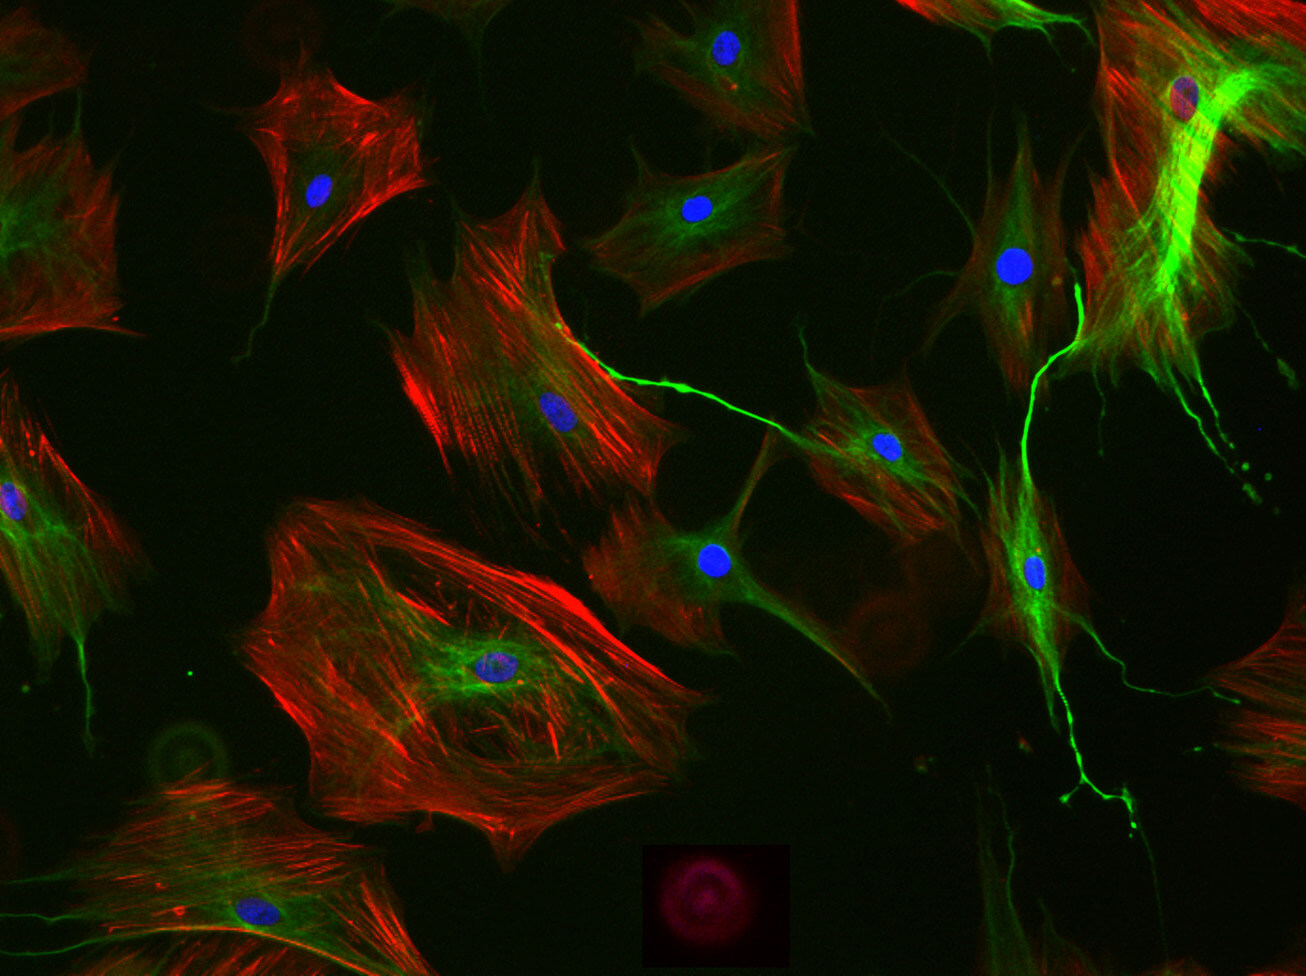

The project tackles its main objective using a multidisciplinary and translational approach. We will use animal models of adverse experiences using transgenic mice, combining molecular, structural and connectivity analyses with superresolution microscopy, behavioral tests and transcriptomics. The project also includes analyses of the thalamus of patients using postmortem tissue. Clinical studies will be also performed in living patients using psychological evaluations, expression analysis in blood and in olfactory neurons of genes relevant to thalamic function/plasticity and DNA methylation analysis of candidate genes. We also plan to generate IPSC cells from patients and, through a collaboration, generate thalamic organoids to study gene expression and connectivity. We will also analyze neuroimaging data in structural and functional MRI from patients to determine changes in different thalamic nuclei, as well as in their projecting regions in the cerebral cortex. Finally, we will perform correlation analyses of all neuroimaging, gene expression, epigenetic and organoid data. The project will be performed both in its basic and its clinical parts on males and females.